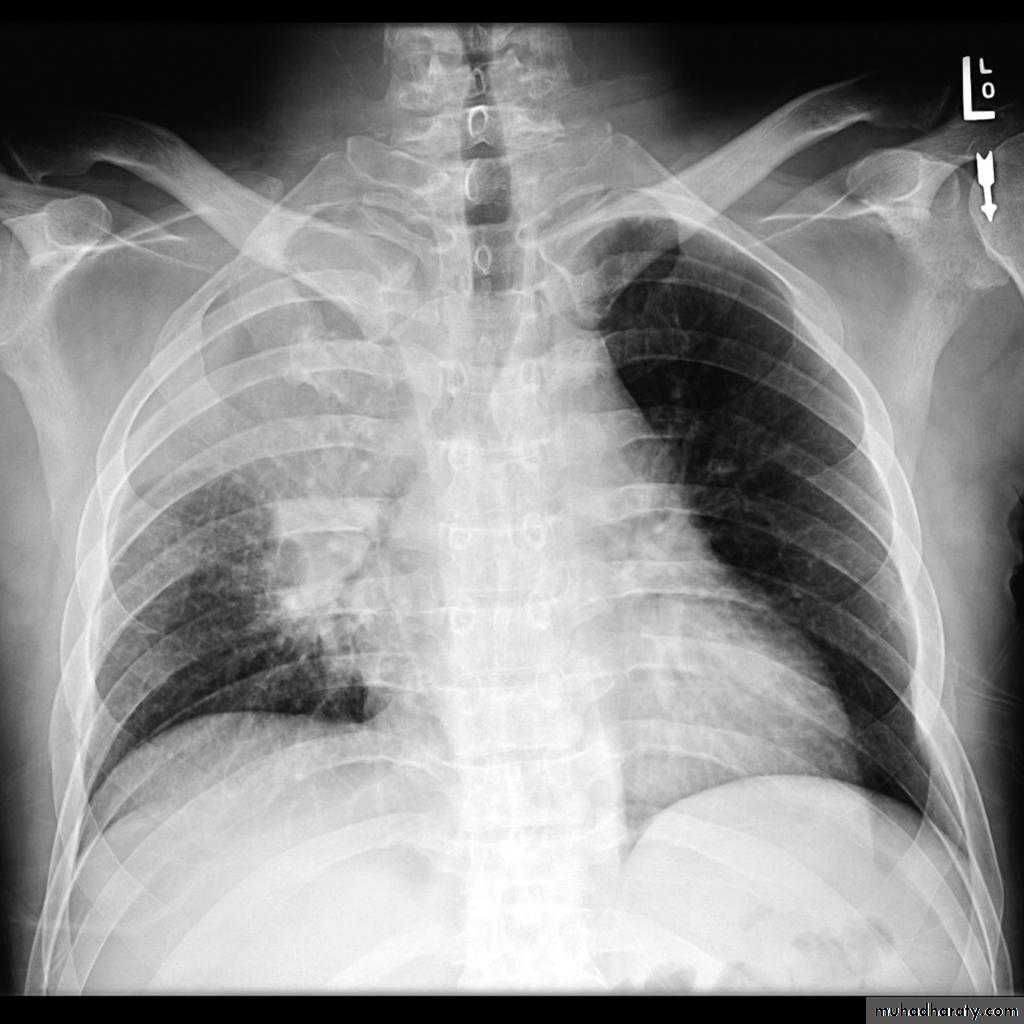

Tension pneumothorax

56.tension pneumothorax left sided aspect

57. tension pneumothorax right sided aspect